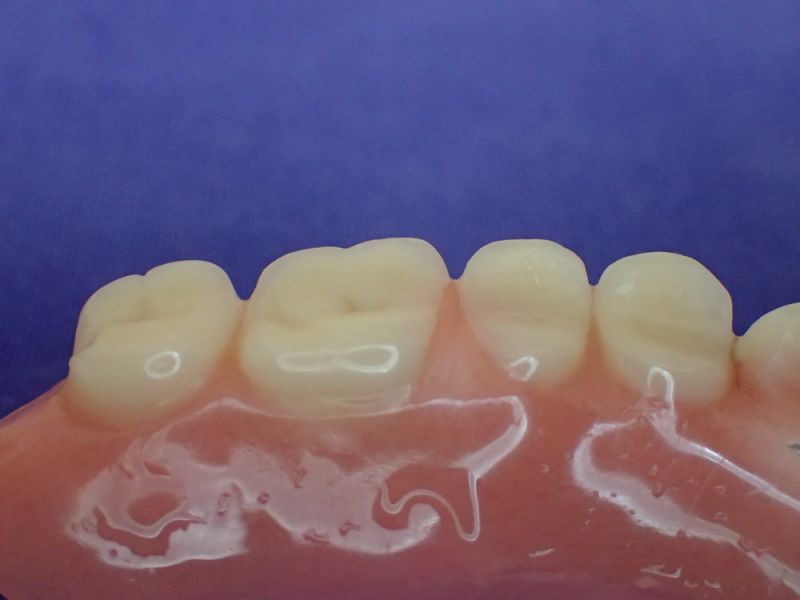

2007 wurde diese implantatgestützte Versorgung erstellt. Die 8 Implantate wurden allesamt hier inseriert und befinden sich bis heute, vollkommen unverändert in Funktion.

Nach inzwischen 12 jähriger Tragedauer wurden alle Kunststoffteile erneuert, das metallische Grundgeroüst der Arbeit erhalten und die Arbeit befindet sich in einem Zustand, der sich weitgehend an der Ersterstellung orientiert.

Bei derartigen Arbeiten ist es tatsächlich möglich grundlegende Konstruktionsmerkmale einer alten Arbeit zu übernehmen und Verschleißteile aus Kunststoff zu erneuern.

Im Prinzip ist das beliebig oft möglich und für den Patienten mit einer enormen Kostenersparnis verbunden.